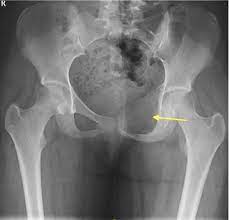

Signs Of Bone Cancer In Pelvis : Free Resources For Medical Professionals Bone Cancer Research Trust / Find out about the symptoms, causes, and treatment of chondrosarcoma, a type of bone cancer most common in your pelvis, thighbone, or upper arm.. It can spread to distant organs, such as the lungs. Pain in the affected bone is the most common sign of bone cancer. People with bone sarcoma may experience the following symptoms or signs. At first, the pain is not constant. Metastatic cancer can spread to any bone, but it most often spreads to bones in the middle of the body.

The amount of pain will vary from person to person. It can be found in the tissue outside the bone, though this is rare. The most common symptom of these cancers is bone pain or swelling in the pelvic area. Fsa tumors are found commonly around the skull, pelvis, spine and ribs. Bone pain may be hard to differentiate from ordinary low back pain or arthritis.

Bone cancer is rare, making up less than 1 percent of all cancers. Bone pain this is often the first and most common symptom. Pain, fever, and fatigue are all symptoms associated with pelvic bone cancer. Find out about the symptoms, causes, and treatment of chondrosarcoma, a type of bone cancer most common in your pelvis, thighbone, or upper arm. This is true of many different pelvic cancer symptoms and may include urinary incontinence, pain and feelings of fullness in the abdomen. Joint swelling and stiffness which may be the result of a tumor located near or in the joint a lump in the back of the throat if there is cancer in the bones of the neck. The usual treatment for bone cancer is surgery, and it has a good outlook. It can spread to distant organs, such as the lungs. In contrast, some other metastatic tumors, such as those from the prostate, are commonly osteoblastic, meaning that they form new bone and increase the brittleness of the bones. Acute lameness may be due to a bone fracture hard, obvious swelling over a long bone of a limb loss of appetite and significant weight loss Signs and symptoms of bone cancer. Symptoms of chondrosarcoma and osteosarcoma chondrosarcoma (cancer of the cartilage) and osteosarcoma (cancer of the bone) are cancers that occur most often in the pelvis, as well as the upper leg and shoulder. Rheumatic disease, arthritis or other conditions that affect the tendons surrounding the hip and the hip joint can also cause limping.

People with bone sarcoma may experience the following symptoms or signs. If bone metastasis affects your bone marrow, you may have other symptoms that are caused by lower blood cell counts. A few other early signs may include: Sometimes, people with bone sarcoma do not have any of these changes. When a bone tumor grows, it presses on healthy bone tissue and can destroy it, which causes the following symptoms: As the cells continue to lump together, the area within the bone swells, making it stiff and tender to touch. The most common symptom of these cancers is bone pain or swelling in the pelvic area. Joint swelling and stiffness which may be the result of a tumor located near or in the joint a lump in the back of the throat if there is cancer in the bones of the neck. It may be worse at night or when the bone is used, for instance, leg pain when walking. Pain in the affected bone is the most common sign of bone cancer. It can be found in the tissue outside the bone, though this is rare. Pain caused by bone cancer usually begins with a feeling of tenderness in the affected bone. Bone pain can cause a dull or deep ache in a bone or bone region (e.g., back, pelvis, legs, ribs, arms).

Cervical Cancer Signs Symptoms And Complications from www.verywellhealth.com Bone cancer can begin in any bone in the body, but it most commonly affects the pelvis or the long bones in the arms and legs. Bone pain is caused by stretching of the periosteum (thick membrane that covers bone) by the cancer, or by stimulation of nerves within the bone. Signs and symptoms of bone cancer. As the cells continue to lump together, the area within the bone swells, making it stiff and tender to touch. Bone pain this is often the first and most common symptom. If white blood cells are affected, you may get infections. At first, the pain is not constant. Osteosarcoma is probably the most common disease that is related to pelvic bone cancer, with chondrosarcoma following close behind it.